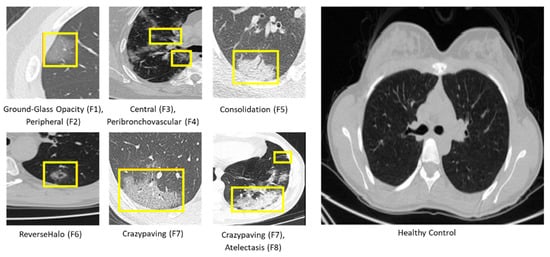

| Feature | Explanation | Symbol |

|---|---|---|

| Ground-Glass Opacity | The hazy gray indicates increased density inside the lungs [25]. | F1 |

| Peripheral | The feature is situated on the edge or periphery of the lung. | F2 |

| Central | The feature is located in the middle of the lung. | F3 |

| Peribronchovascular | Thickening of the interstitial or bronchial wall [28]. | F4 |

| Consolidation | The alveolar air spaces are filled with fluid, cells, tissue, or other material [29]. | F5 |

| Reverse Halo | Central ground-glass opacity surrounded by denser consolidation of a crescent shape or a complete ring of at least 2 mm in thickness [30]. | F6 |

| Crazy Paving | Scattered diffuse ground-glass attenuation with superimposed interlobular septal thickening and intralobular lines [31]. | F7 |

| Atelectasis | Complete or partial collapse of the entire lung or area(lobe) of the lung [32]. | F8 |